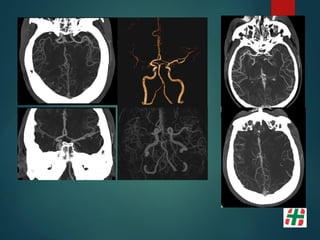

Patología Aneurismática

 Dilatación vascular que afecta solo una porción del

perímetro vascular.

 Carece de lámina elástica y ± túnica media.

 Se los clasifica básicamente en:

 Sacular;

 Ampollar;

 Fusiforme.

Pericallosa 4%

Comunicante Anterior 30%

Bifurcación ACI 7.5%

ACM 20%

Comunicante

Posterior 25%

Tope Basilar 7%

PICA 3%

Otras 3,5%

Brisman, et al. N Engl J Med 2006;355:928-39.

Métodos diagnósticos

 Angiografía Digital (3D DSA);

Sensibilidad del 96% lesiones del 0.5 a 4 mm.

 TC, Angio TC (Multidetector);

Sensibilidad del 40% al 97%.

Patología Aneurismática  Dilataciónvascular que afecta solo una porción del perímetro vascular.  Carece de lámina elástica y ± túnica media.  Se los clasifica básicamente en:  Sacular;  Ampollar;  Fusiforme.

Pericallosa 4% Comunicante Anterior30% Bifurcación ACI 7.5% ACM 20% Comunicante Posterior 25% Tope Basilar 7% PICA 3% Otras 3,5% Brisman, et al. N Engl J Med 2006;355:928-39.

Métodos diagnósticos  AngiografíaDigital (3D DSA); Sensibilidad del 96% lesiones del 0.5 a 4 mm.  TC, Angio TC (Multidetector); Sensibilidad del 40% al 97%.  Angio RM (T.O.F.) Sensibilidad 38% lesiones al 94%